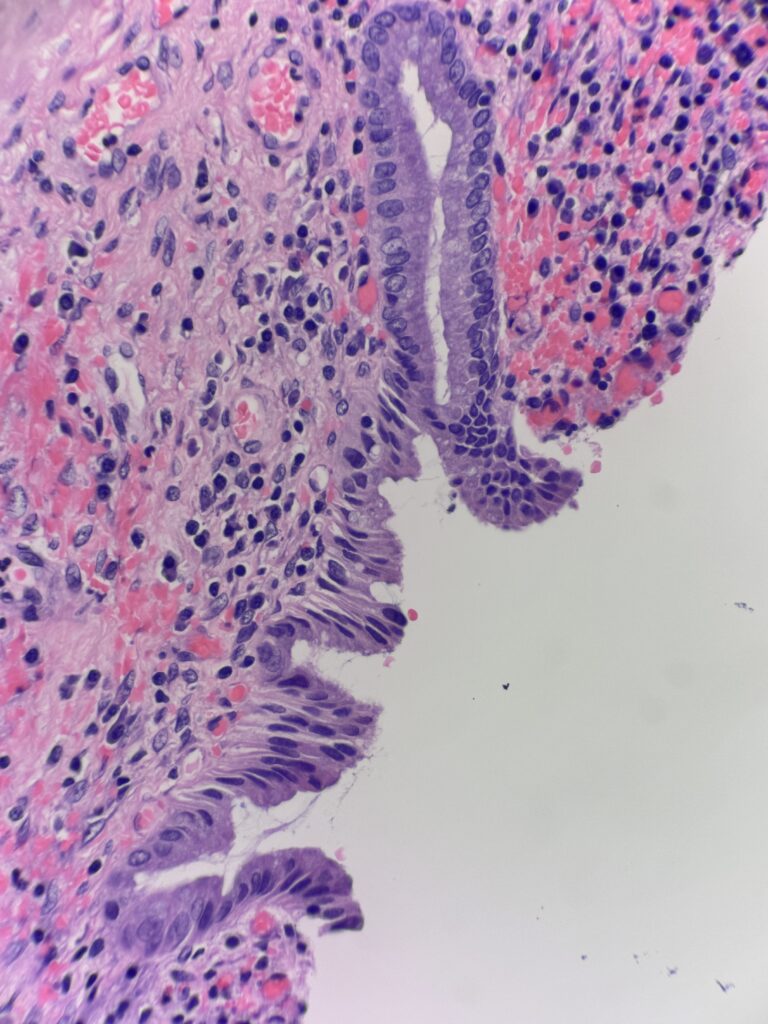

History: 44 y/o female presents with biliary colic and undergoes a cholecystectomy

Diagnosis: Xanthogranulomatous cholecystitis

The first image shows gallbladder mucosa with chronic inflammation and reactive epithelial changes. The following images show regions deeper in the submucosa and muscularis consisting of nodular aggregates of foamy histiocytes. These cells are positive for CD68 and negative for pankeratin – to differentiate this inflammatory entity from an infiltrating carcinoma.